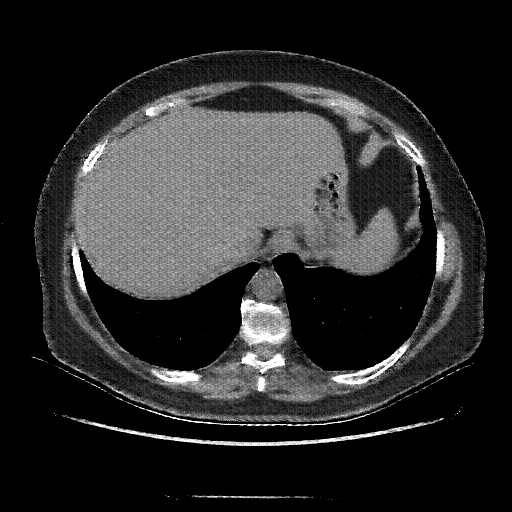

Original VENOUS CT scan

Full window (WL 1023.5, WW 4095 β†’ Low βˆ’1024, High +3071)

Actual HU range: [-1024.0, 884.0]